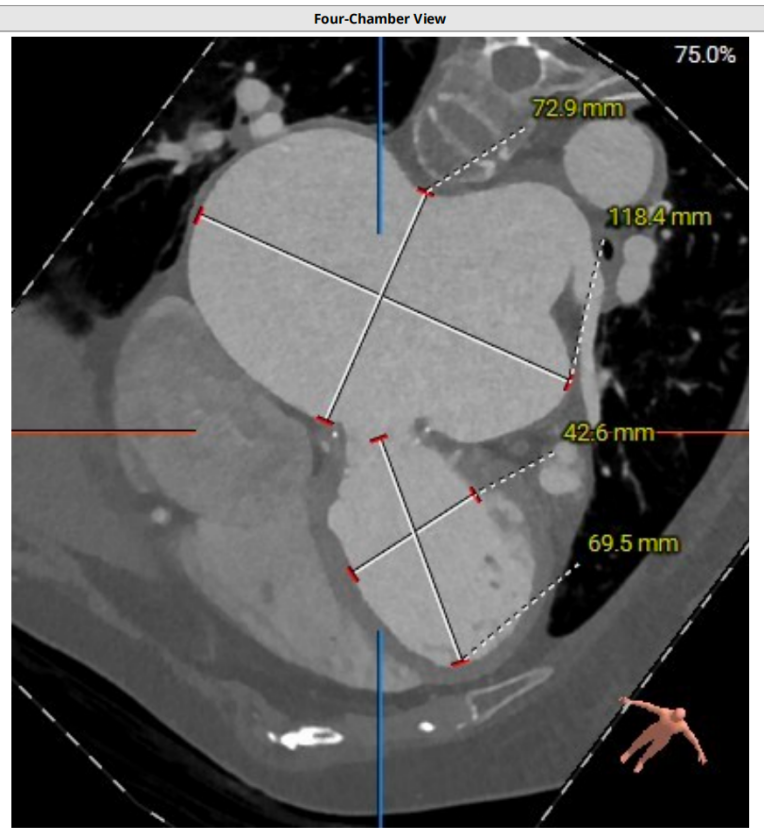

术前CT评估

二尖瓣生物瓣支架内径 26.5mm,结合瓣架形态、瓣架高度及手术记录,符合EPIC 27#。瓣中瓣治疗考虑选择25# 介入瓣膜。模拟25# 瓣膜植入,测得NEO-LVOT 面积155.8mm²,术后存在新流出道梗阻风险。左心耳尖端未见血栓。左心房增大73.4*118.7mm,房间隔未见增厚,未见明显钙化,靠后靠下房间隔穿刺点距二尖瓣水平高度27.7mm,房间隔穿刺点高度可。